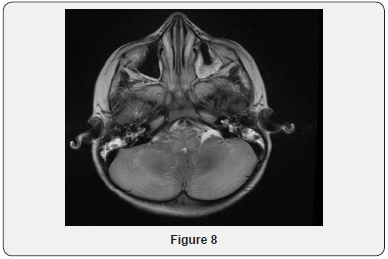

Echocardiogram Holter monitor and Eye examination all were normal. The patient underwent muscle biopsy which showed mild lipid myopathy with type 2 muscle fiber atrophy, but with no morphological evidence of mitochondrial disease. A stat CT brain showed hemorrhagic infarction and some fresh bleeding in subarachnoid space (not older than 3 days), possibly on the basis of ischemic lesions, considering the further hypodense lesions in the parasagittal area on bi-occipital and parieto-occipital regions, more extended on the left side (Figure 4). The neurosurgery team was notified, but it was determined that the patient has poor prognosis and is not candidate for surgery. Gradually, the patient developed respiratory distress and was transferred to the intensive care unit and required mechanical ventilation. He was monitored continuously by EEG. At that time, he showed subclinical seizures originating from the posterior head region, right side more than left. A burst suppression pattern was established, but during the burst period he was having multifocal spikes and polyspikes. Brain MRI showed massive hemorrhagic infarction of non-vascular distribution pattern involving the posterior occipito-parietal, region with brain stem area and cerebellum (Figures 5-9) and a lesion extending to the temporo-parietal region (Figures 5,7). Cerebral angiography showed multiple territorial hemorrhagic infarctions, with no blood entering intracranially in a case of massive intracranial edema, suggesting brain death (Figure 10). Using homozygosity mapping followed by whole exome sequencing, we identified a homozygous mutation of APOA1BP that caused lethal infantile leukoencephalopathy. The patient continued to deteriorate, then died at the age of four years.